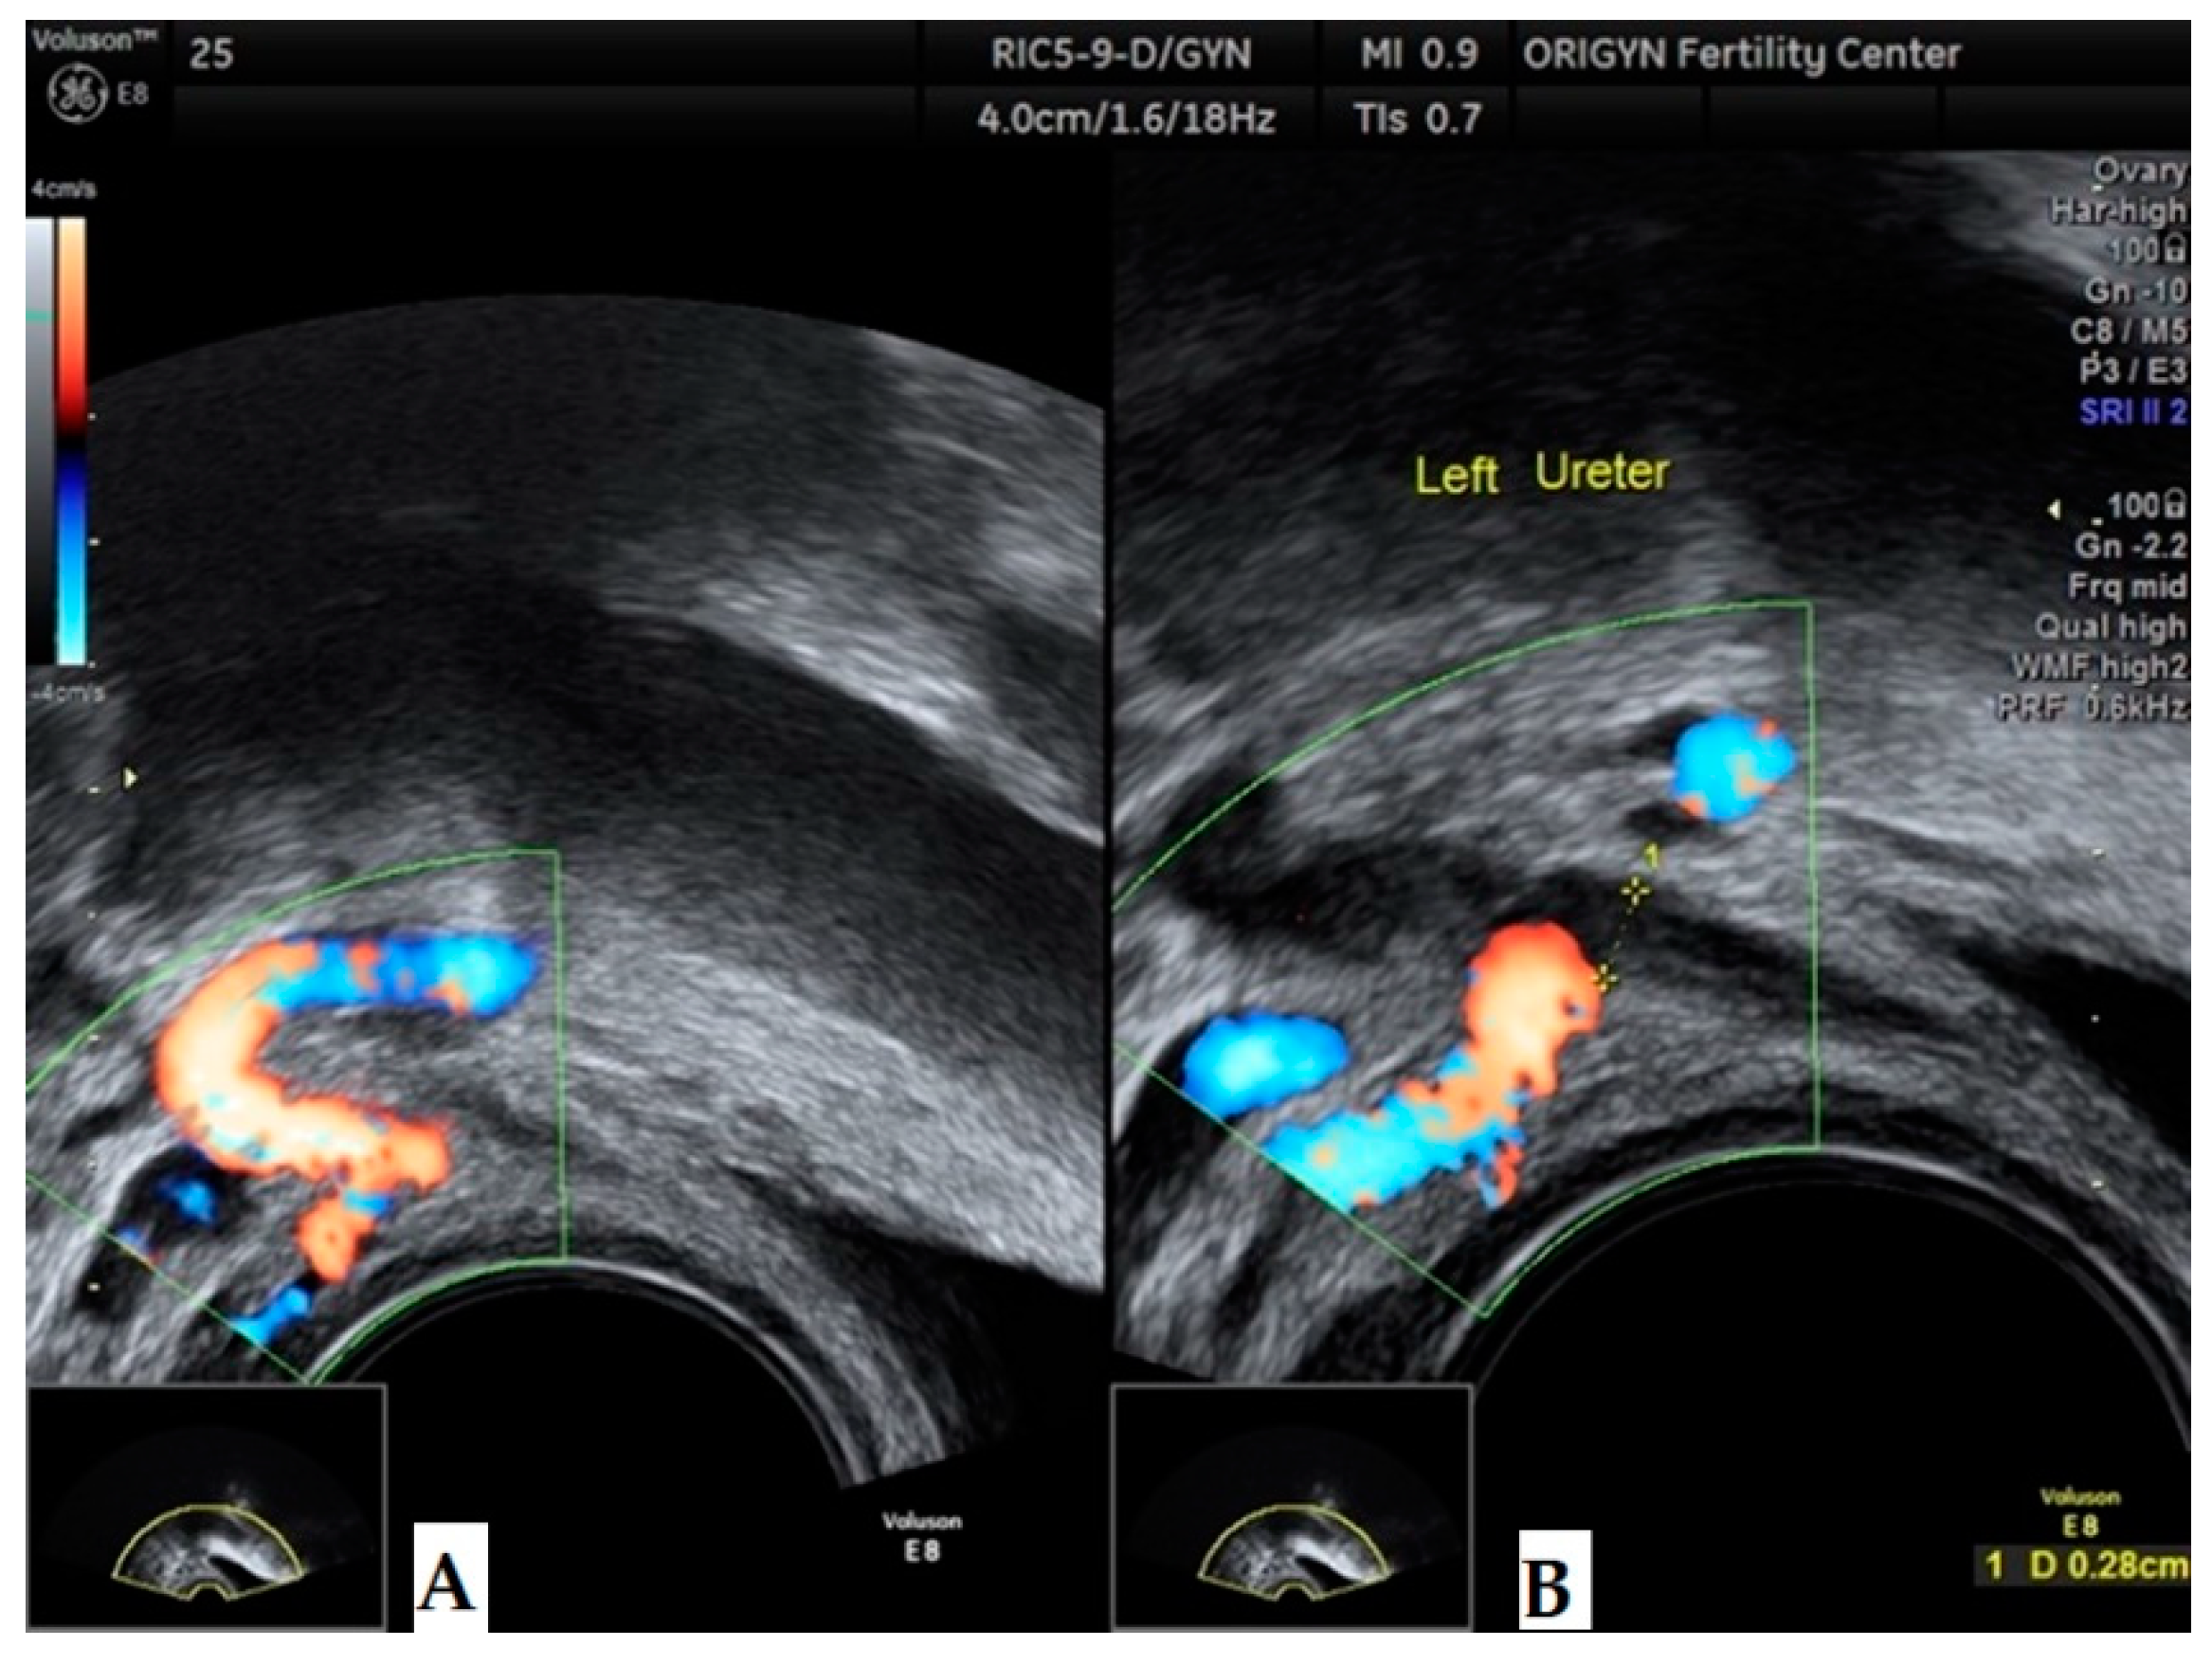

3.1. ADNEXA